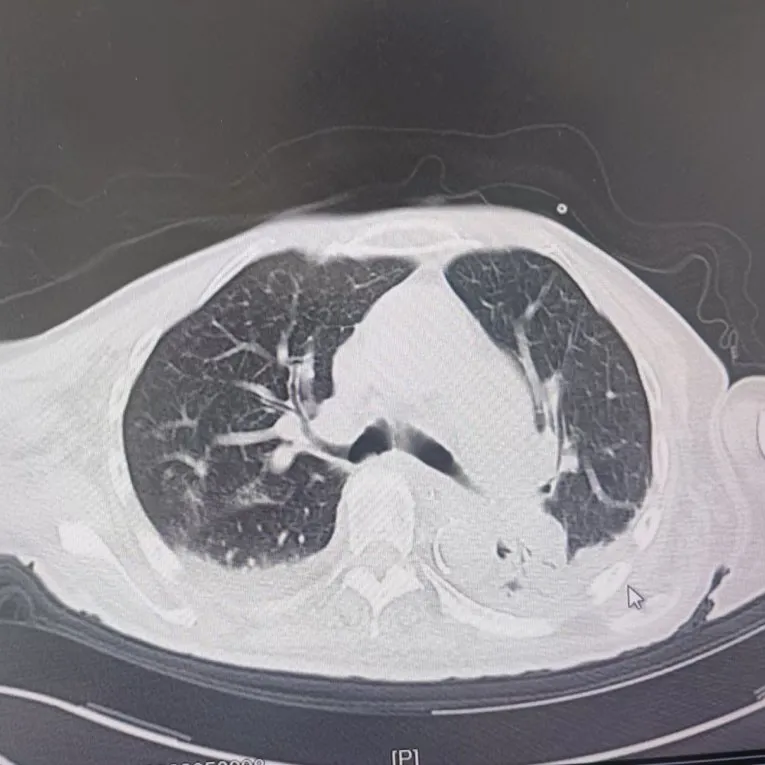

引言 / / Introduction 年近8旬的陳阿姨(化名)因腦梗長(zhǎng)期癱瘓?jiān)诖?,康?fù)期間突然高燒不退,體溫升至39℃,在抗感染過(guò)程中,她并發(fā)高滲性脫水,病情急劇惡化,被緊急送入ICU。此時(shí),她已氣管切開(kāi),依靠呼吸機(jī)維持呼吸,并伴有低蛋白血癥、低鉀高鈉血癥及房顫等多種危重情況,命懸一線! PART. 01 多重泛耐藥菌疊加大量基礎(chǔ)病 治療陷入“死胡同” 呼吸與危重癥醫(yī)學(xué)科及ICU通力協(xié)作,穩(wěn)住患者生命體征。治療過(guò)程中,進(jìn)一步的病原學(xué)檢查結(jié)果令人心驚:陳阿姨的肺部遭遇多種“超級(jí)細(xì)菌”混合侵襲,包括銅綠假單胞菌、鮑曼不動(dòng)桿菌、嗜麥芽窄食單胞菌、金黃色葡萄球菌、木糖氧化無(wú)色桿菌、粘質(zhì)沙雷菌等高度耐藥菌,堪稱(chēng)耐藥菌“大本營(yíng)”。這些細(xì)菌對(duì)常用抗生素幾乎全部耐藥,治療難度高,死亡率高。 治療前患者肺部影像 PART. 02 多學(xué)科強(qiáng)強(qiáng)聯(lián)手 量身定制攻堅(jiān)方案 面對(duì)無(wú)藥可用的困境,呼吸科沒(méi)有放棄!宋剛主任帶領(lǐng)團(tuán)隊(duì)聯(lián)合藥學(xué)部、檢驗(yàn)科、重癥醫(yī)學(xué)科成立多學(xué)科治療組,根據(jù)患者身體情況實(shí)時(shí)調(diào)整用藥,逐一攻破耐藥菌。這場(chǎng)與“超級(jí)細(xì)菌”的拉鋸戰(zhàn)持續(xù)了30多個(gè)日夜。 在醫(yī)護(hù)日夜堅(jiān)守和家屬全力配合下,陳阿姨的感染終于被遏制:高燒退了,肺部陰影消散了!就在即將宣告勝利時(shí),又發(fā)現(xiàn)她存在泌尿感染問(wèn)題,隨即轉(zhuǎn)入泌尿外科協(xié)同治療。當(dāng)宋主任回訪時(shí),看到陳阿姨精神煥發(fā)、體溫平穩(wěn),所有參與救治的人都感慨萬(wàn)分!這場(chǎng)救治,正是呼吸與危重癥醫(yī)學(xué)科攻堅(jiān)耐藥菌硬實(shí)力的生動(dòng)體現(xiàn)! 治療后患者肺部影像 從“無(wú)藥可用”到“絕處逢生”,此次成功救治,集中體現(xiàn)了呼吸與危重癥醫(yī)學(xué)科以耐藥菌精準(zhǔn)診治為核心的學(xué)科特色與技術(shù)優(yōu)勢(shì)。面對(duì)一次次的嚴(yán)峻挑戰(zhàn),科室始終秉持“生命至上、知難而進(jìn)”的信念,以多學(xué)科協(xié)作為平臺(tái),憑借個(gè)體化精準(zhǔn)用藥策略,為患者尋找生機(jī),為更多陷入困境的患者和家庭帶去了實(shí)實(shí)在在的希望。 PART. 03 人民醫(yī)院 人民名醫(yī) 宋剛 主任醫(yī)師 ·葫蘆島市第二人民醫(yī)院呼吸與危重癥醫(yī)學(xué)科主任 ·遼寧省生命科學(xué)學(xué)會(huì)東北呼吸與危重癥醫(yī)學(xué)(PCCM)分會(huì)遼寧省基層委員會(huì)副主任委員 ·遼寧省細(xì)胞生物學(xué)學(xué)會(huì)放射粒子治療專(zhuān)業(yè)委員會(huì)理事 ·遼寧省抗擊新冠肺炎疫情先進(jìn)個(gè)人 ·葫蘆島市勞動(dòng)鑒定委員會(huì)專(zhuān)家?guī)斐蓡T ·葫蘆島市醫(yī)學(xué)會(huì)呼吸內(nèi)科學(xué)分會(huì)第三屆委員會(huì)副主任委員 專(zhuān)業(yè)特色:擅長(zhǎng)呼吸系統(tǒng)疑難及急危重患者的救治,如急慢性支氣管炎、支氣管哮喘、慢性阻塞性肺疾病、肺炎、肺栓塞、肺癌、間質(zhì)性肺疾病、睡眠呼吸暫停綜合征等,尤其擅長(zhǎng)有創(chuàng)無(wú)創(chuàng)機(jī)械通氣、支氣管鏡下相關(guān)檢查及治療(TBNA、氣道支架置入術(shù)、球囊擴(kuò)張等)、全肺灌洗術(shù)等領(lǐng)先技術(shù),發(fā)表國(guó)家級(jí)期刊多篇。